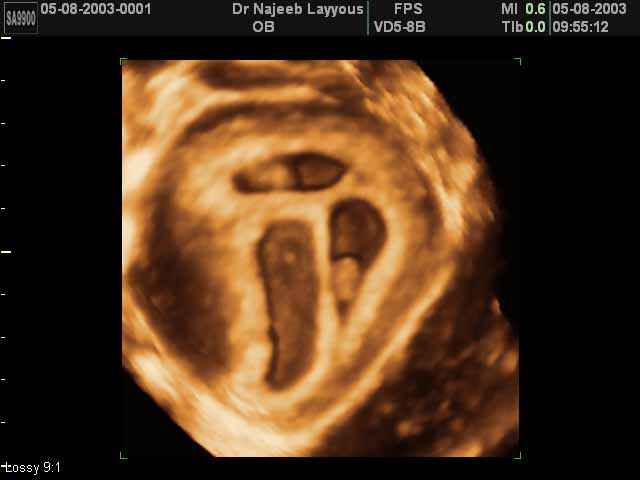

- صور لتوائم

صور لتوائم بجهاز الالتراساوند ثلاثي الأبعاد | الدكتور نجيب ليوس